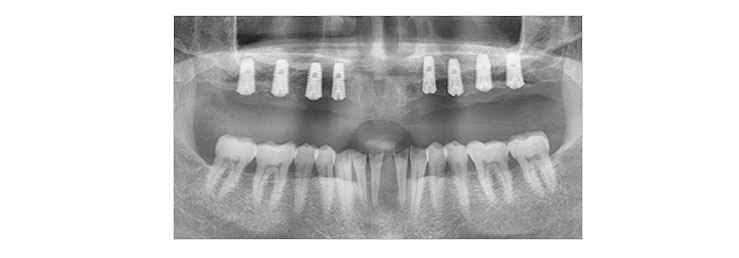

임플란트 식립

1차 수술을 통해 정확한 위치에 임플란트를 심습니다.

임플란트의 골유착 및 지대주의 연결

임플란트 수술 후 골의 치유 및 임플란트의 골유착이 진행되면 2차 수술을 통해 잇몸 밖으로 기둥(지대주)을 연결합니다.

*수술 형태에 따라 2차 수술은 생략될 수 있습니다.